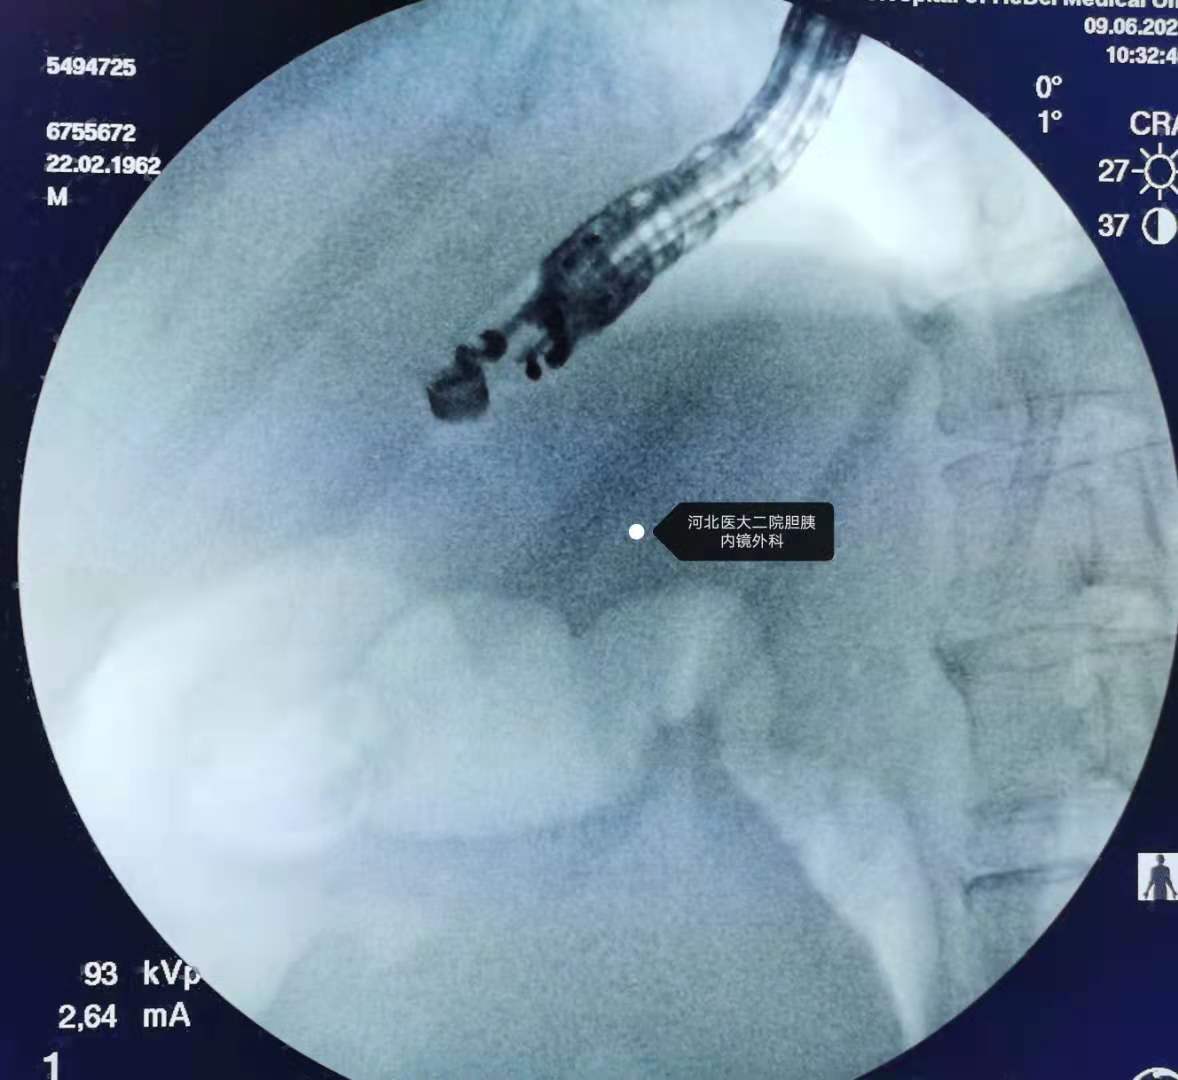

透视下镜子位置。